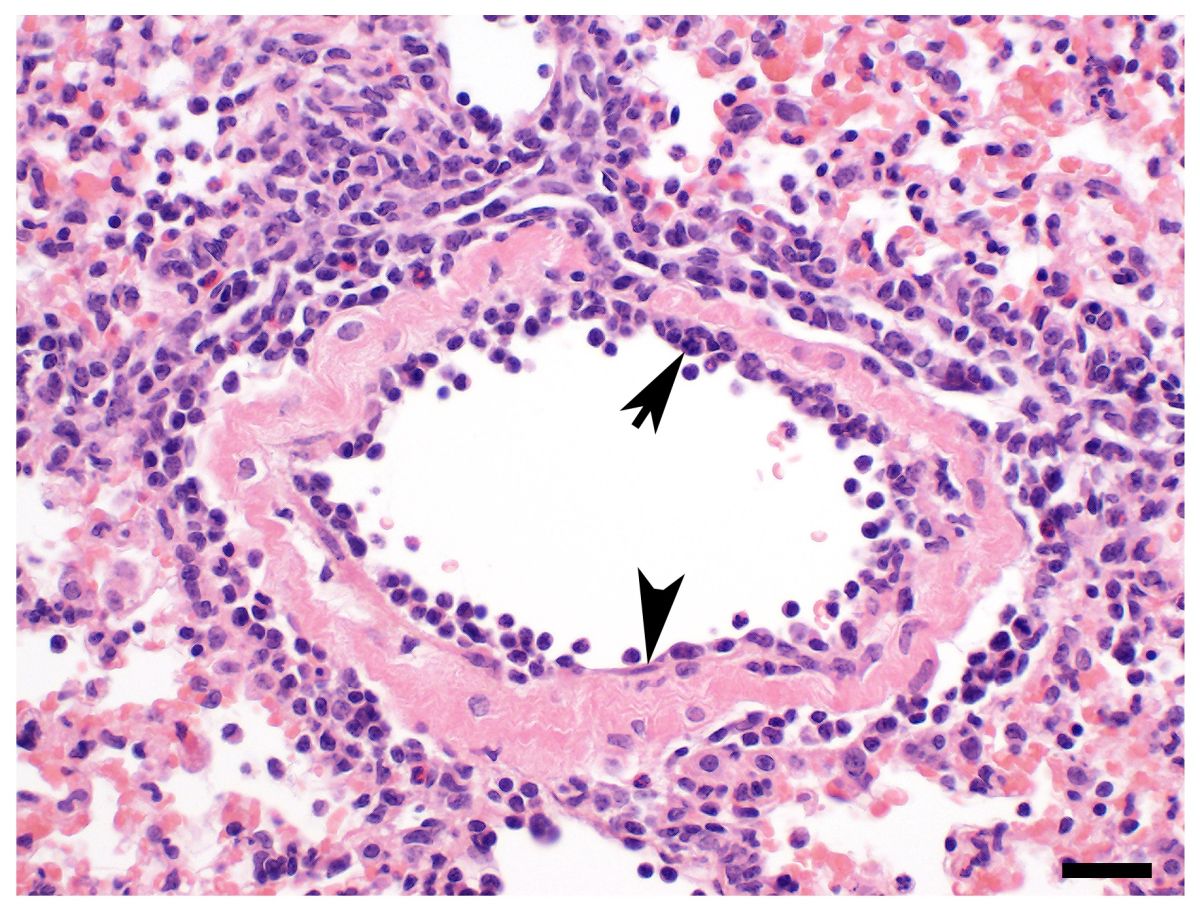

Bei der Mehrheit der Patientinnen und Patienten mit schwerem COVID-19 vernarbt die Lunge in außergewöhnlich starkem Ausmaß. Das zeigen Forschende der Charité – Universitätsmedizin Berlin, des Helmholtz-Instituts für RNA-basierte Infektionsforschung (HIRI), des Max-Delbrück-Centrums für Molekulare Medizin in der Helmholtz-Gemeinschaft (MDC), der Uniklinik RWTH Aachen und des Robert Koch-Instituts in einer aktuellen Studie. Wie sie in der Fachzeitschrift „Cell“ beschreiben, spielen Fresszellen des Immunsystems eine zentrale Rolle. Einige Prozesse des COVID-19-Lungenversagens ähneln dabei denen der idiopathischen Lungenfibrose, einer bisher unheilbaren Form der Lungenvernarbung. Die gestörte Narbenreaktion könnte erklären, warum die Lunge lange funktionsunfähig bleibt und eine langwierige ECMO-Therapie erfordert.

Als Grund für die lange Dauer des Lungenversagens hatte das Forschungsteam unter anderem eine spezielle Form des ARDS im Verdacht, bei der das Lungengewebe vernarbt, dadurch verdickt und unelastisch wird. Schon relativ früh in der Pandemie war bei einzelnen Patient*innen ein solcher als Fibrose bezeichneter Umbau des Gewebes aufgefallen. Die aktuelle Studie des interdisziplinären Forschungskonsortiums aus ganz Deutschland bestätigt nun, dass das schwere COVID-19-bedingte Lungenversagen tatsächlich sehr häufig von einer ausgeprägten Vernarbung des Lungengewebes begleitet wird. „Eine fehlgeleitete Reaktion der Makrophagen, die auch als Fresszellen des Immunsystems bekannt sind, könnte dafür mitverantwortlich sein“, konstatiert Dr. Antoine-Emmanuel Saliba, Arbeitsgruppenleiter am HIRI in Würzburg und zweiter korrespondierender Leiter der Studie.

Proben aus Lungenspülungen und -gewebe

Für die Studie untersuchte das Team die Lungen verstorbener COVID-19-Patienten anhand verschiedener mikroskopischer Aufnahmen. „Bei fast allen Betroffenen haben wir enorme Schäden entdeckt: Die Lungenbläschen waren weitgehend zerstört, die Wände deutlich verdickt. Außerdem fanden wir ausgeprägte Ablagerungen von Kollagen, welches ein Hauptbestandteil von Narbengewebe ist. All dies ist charakteristisch für eine schwere Fibrose“, beschreibt Professor Peter Boor die Befunde. Er hat die Studie am Institut für Pathologie der Uniklinik RWTH Aachen geleitet. „Diese Beobachtungen weisen darauf hin, dass wir es beim COVID-19-Lungenversagen mit einem fibroproliferativen ARDS zu tun haben, also einer besonders schweren Form des Lungenversagens. Das könnte erklären, warum wir die Betroffenen so lange beatmen müssen.“

Der Grund für dieses Phänomen war zunächst unklar. „Bei COVID-19 entwickelt sich ein Lungenversagen typischerweise erst in der zweiten oder dritten Woche nach Symptombeginn, wenn die Viruslast eigentlich schon wieder sinkt“, erklärt Sander. „Das weist darauf hin, dass nicht die unkontrollierte Virusvermehrung zum Versagen der Lunge führt, sondern nachgeschaltete Reaktionen, beispielsweise des Immunsystems, eine Rolle spielen.“ Die Wissenschaftlerinnen und Wissenschaftler analysierten deshalb die Zusammensetzung und Eigenschaften der Immunzellen in Lungenspülungen und -gewebe schwer erkrankter beziehungsweise verstorbener COVID-19-Patient*innen. Dazu nutzten sie modernste Methoden der Einzelzellanalyse. Mit ihnen ist es möglich, jede einzelne Zelle im Detail zu betrachten.

SARS-CoV-2 programmiert die Immunzellen um

Das Team konnte so zeigen, dass sich in der Lunge von COVID-19-Betroffenen, die ein Lungenversagen entwickeln, vor allem Makrophagen in großen Mengen ansammeln. Diese Fresszellen beseitigen zum Beispiel eingedrungene Erreger oder Zellabfall, sind aber auch an der Wundheilung und Reparatur von Gewebe beteiligt. „Überraschenderweise zeigten die Makrophagen bei schwerem COVID-19 ähnliche Eigenschaften wie bei einer chronischen Form der Lungenvernarbung, der idiopathischen Fibrose“, betont Saliba. Bei dieser unheilbaren Erkrankung vernarbt die Lunge unaufhaltsam bis zum Verlust der Organfunktion. Die Ursache ist unbekannt, unter allen Formen der Lungenfibrose hat sie die schlechteste Prognose. „Die Makrophagen treten bei schwerem COVID-19 mit bestimmten Zellen des Bindegewebes in Kontakt, die für die Bildung von Narbengewebe verantwortlich sind. Diese Zellen vermehren sich stark und produzieren große Mengen Kollagen“, ergänzt der Experte der Einzelzellforschung.